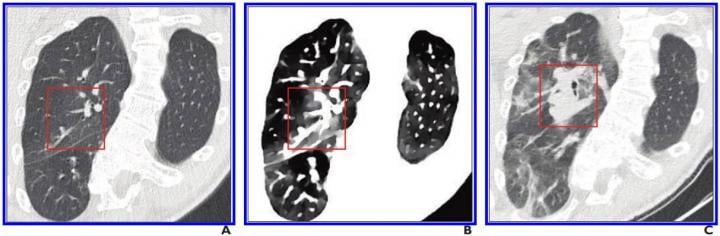

This photo gallery shows the variety of radiological presentations of COVID-19 (SARS-CoV-2) in medical imaging, including computed tomography (CT), radiograph X-rays, ultrasound, echocardiograms and magnetic resonance imaging (MRI). The radiology images show examples of typical COVID pneumonia in the lungs and the numerous complications the virus causes in the body in multiple organs, including the brain, kidneys, heart, abdomen and vascular system.

Ultrasound, especially hand-held ultrasound imaging devices, have become a primary imaging modality for novel coronavirus because of the ease to bag the device and sterilize it after use. CT and mobile X-ray systems are also used as front-line imaging systems for COVID-positive or suspected COVID patients.

The images were collected from physicians, study authors, universities and hospitals, the National Institutes of Health (NIH), the Radiological Society of North America (RSNA), the American College of Radiology (ACR), Centers for Disease Control and Prevention (CDC) and radiology technology vendors.